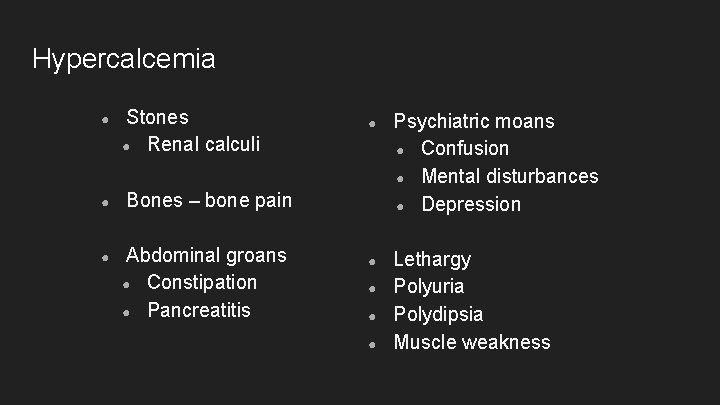

Hypercalcemia ● ● ● Stones ● Renal calculi ● Psychiatric moans ● Confusion ● Mental disturbances ● Depression ● Lethargy Polyuria Polydipsia Muscle weakness Bones – bone pain Abdominal groans ● Constipation ● Pancreatitis ● ● ●